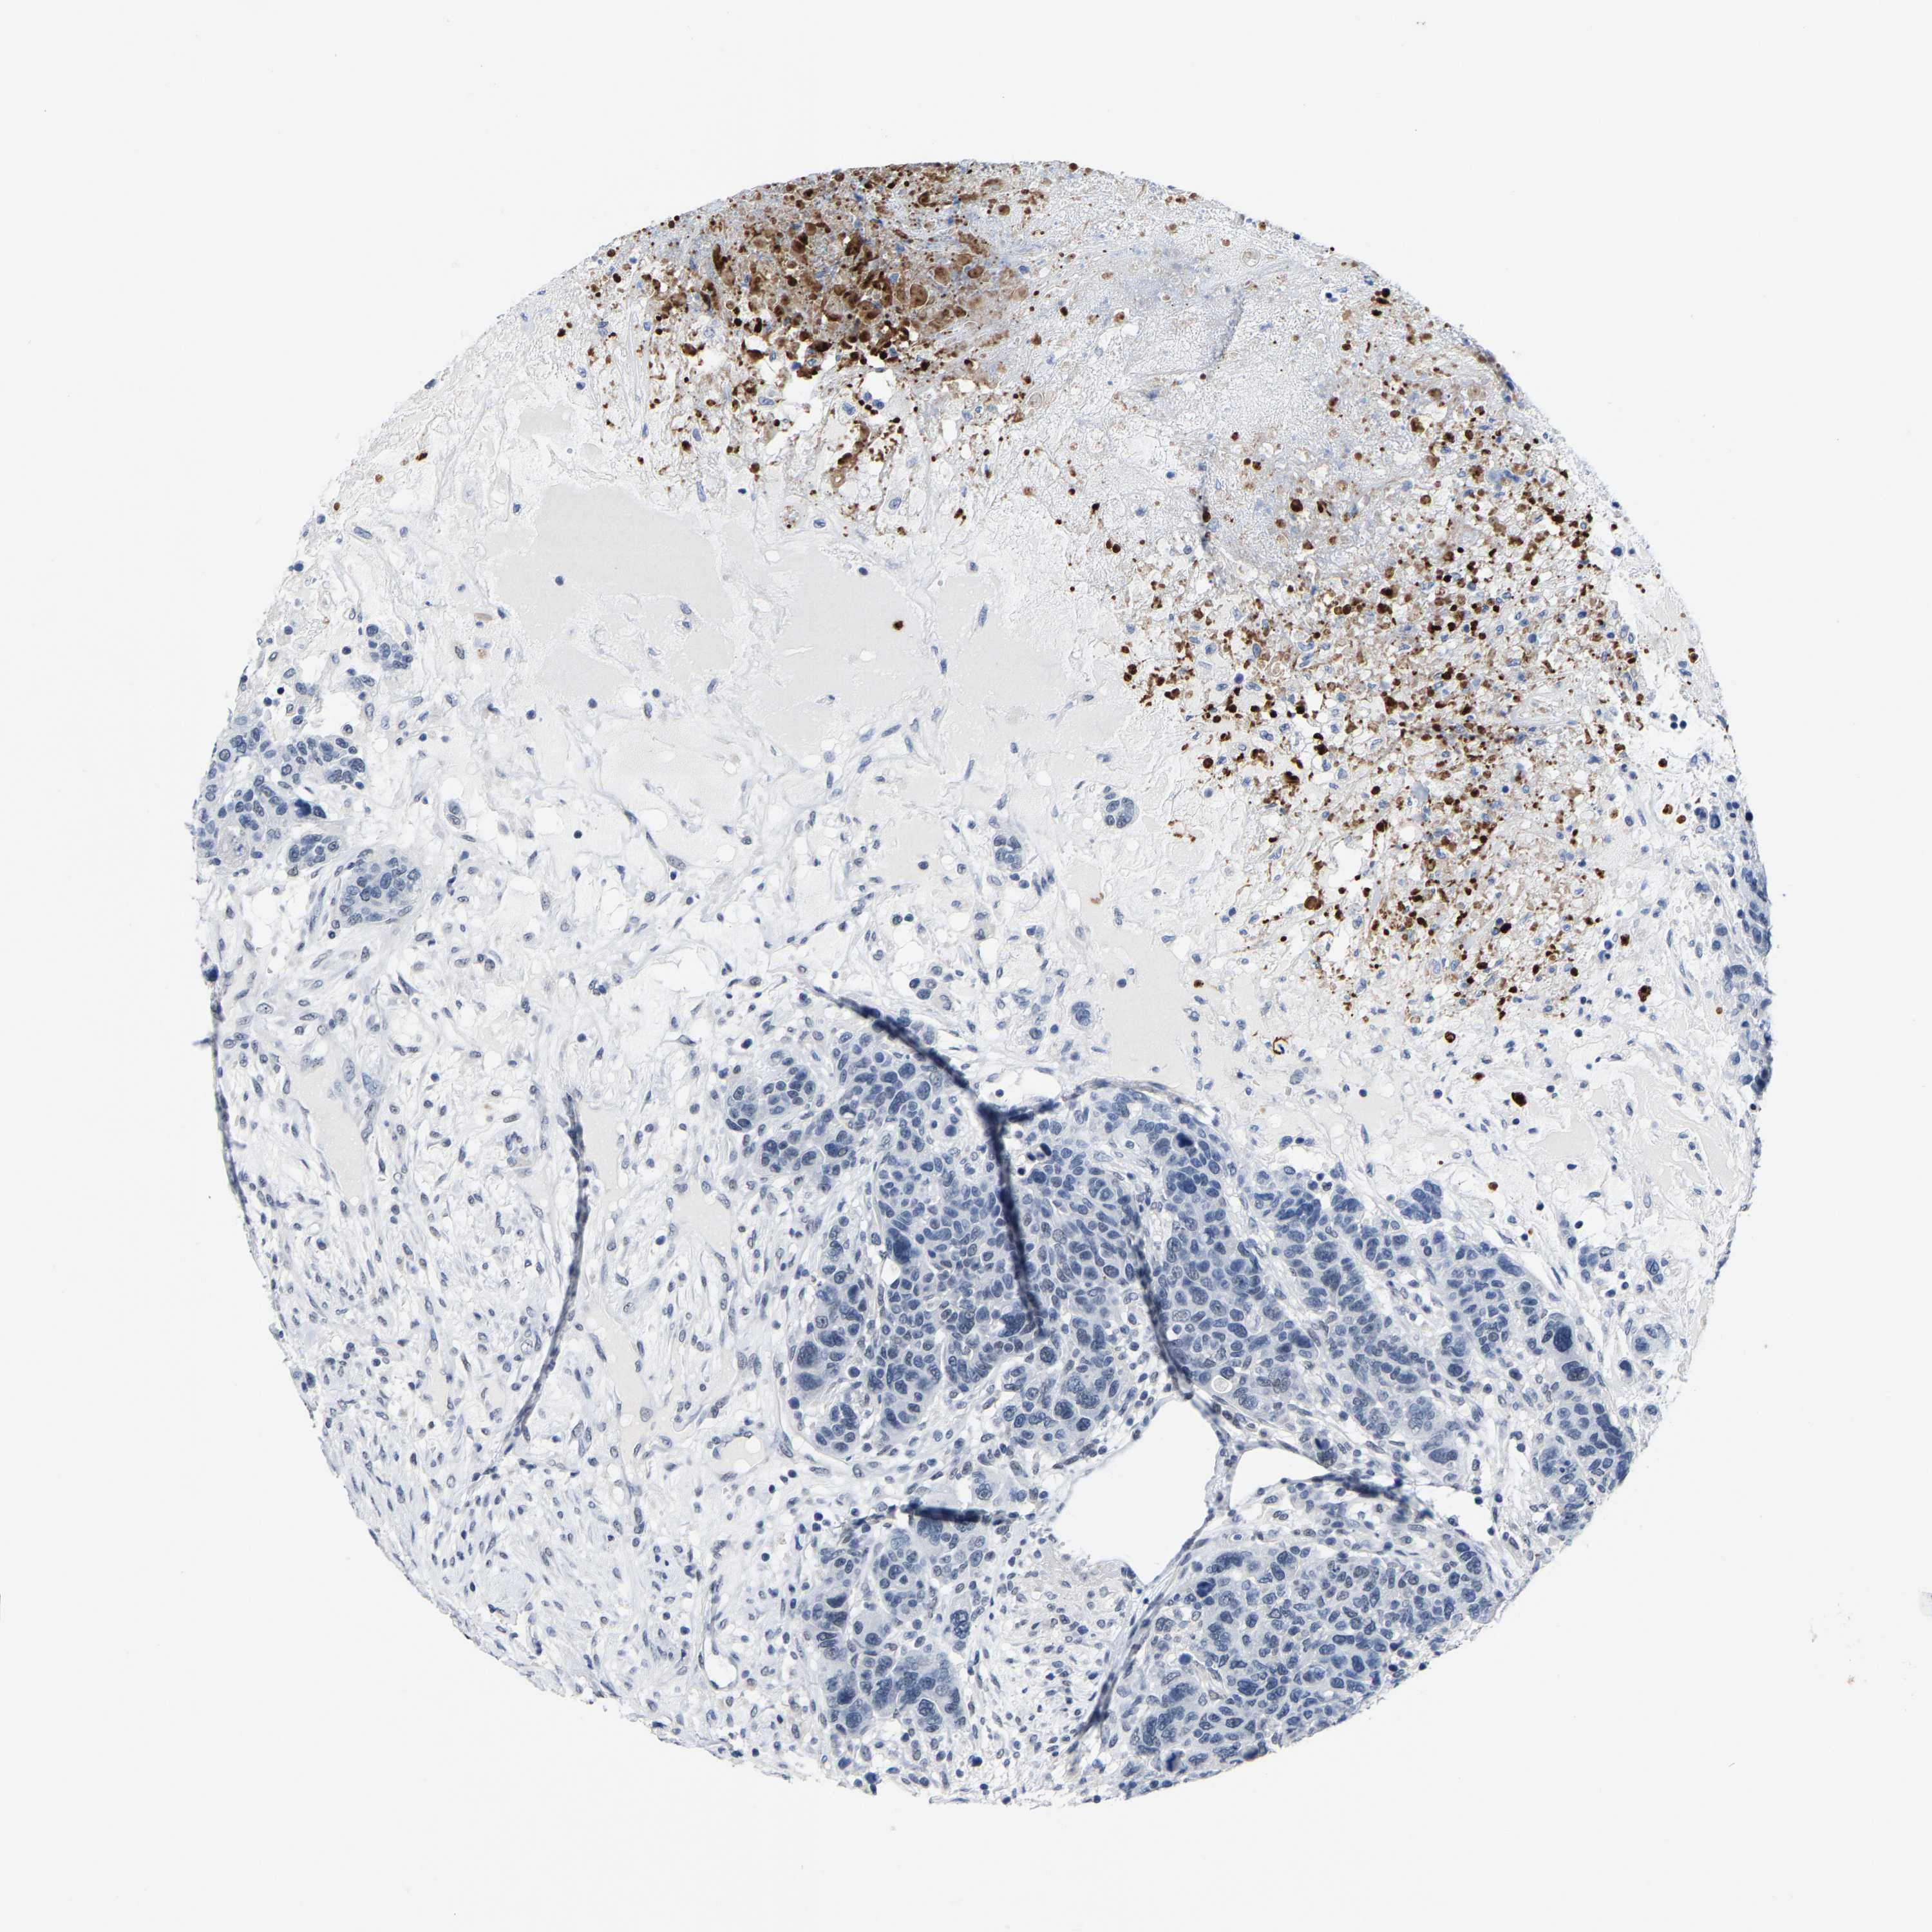

BRCA TCGA BRCA VALIDATION PROTEIN EXPRESSION